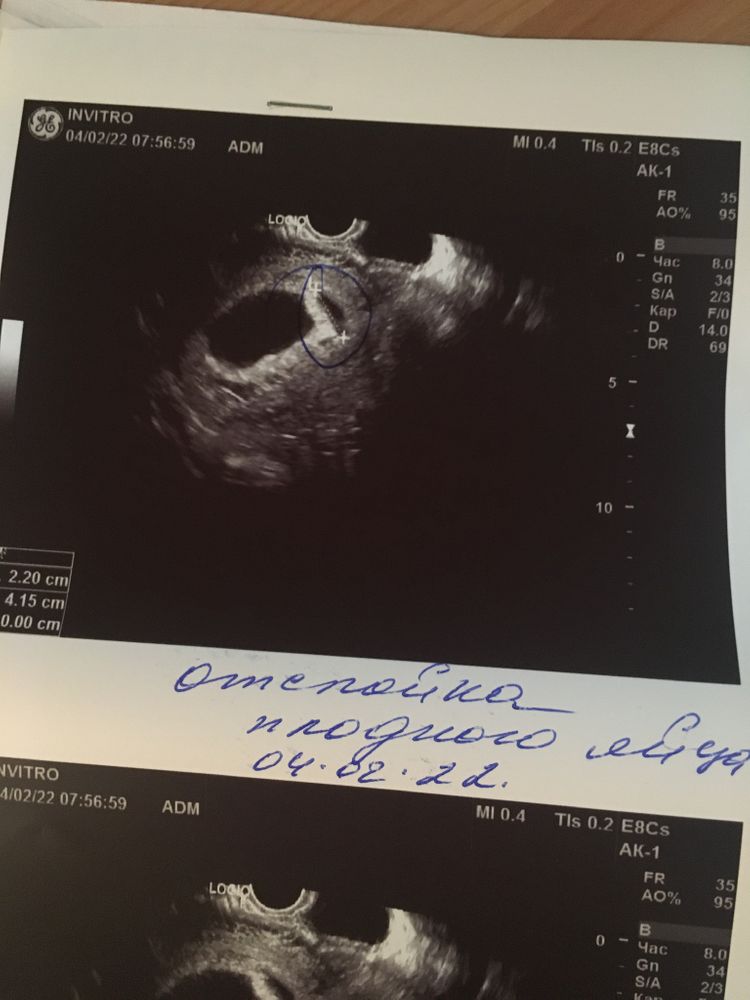

Токсикоз и усталость есть, но не все так плохо. Сходила на узи в 7+2, подтвердили маточную беременность, сказали, что есть небольшая отслойка и лучше принимать дюфастон по 2 таблетки, больше лежать. Ну это я сама виновата, поднимала уже совсем нелегкого сына. ХГЧ был высоким, но не из-за двойни, а ранней овуляции, до сих пор не понимаю, когда она у меня произошла(во время м?), срок по узи 7+5, даже больше, чем акушерский.